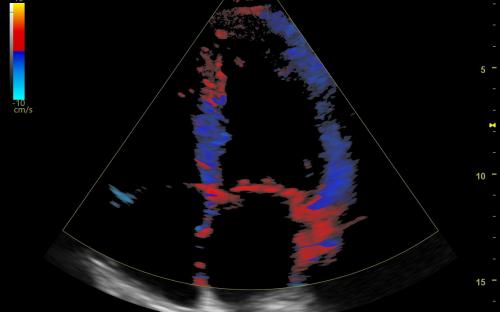

查看完整图像 超音频多功能图像系统 弗尼泽: 通用电气医疗 分类: 超声造影 水平标签 描述 凡尔赛那平衡是一个多功能生态系统,用于完成腹部检查、产科工程、口腔、肌肉、血管、泌尿、儿科和心脏病的检查。 Av和un设计工效学-现代、环保的成人能力-卓越的稳定性-诊断、快速、精确、分散和功能变化: 乳房护理/甲状腺生产力-分析模块,特别是在不同类型的系统中 B-流量-独立于生态技术的多普勒利用率评估血管结构 自动IMT-网络媒体自动管理模块 针识别-生物程序的虚拟化模块 自动EF-分析心脏变形的仪器,用于分析心室破裂的结石 Mod de analiză4DVizaliza toate cele 3 planuri ale structurilor Anomologie,av–and Utiliteîn specialîn aplicațiile de Occomaticăi de ginecologie 想象临床 查看完整图像 查看完整图像 查看完整图像 查看完整图像 德斯卡ă 描述: 韦尔萨纳兄弟天平 韦尔萨纳兄弟家族 教育 通用平台是一个可持续发展的教育支持平台,它是一个可持续发展的生态系统的应用平台,它是一个信息产业的发展平台,也是一个医疗实践的平台,在Versana ecografele中,阿替卡因和阿替卡因是一种具有丰富经验的药物。 特别是注册简单的VersanaClub depăeșeșe Barirele de timpși spași uneșutilizatori de ecografe Versana pentru联合国医疗卫生标准法案。 联邦登记局链接:https://www.versanaclub.net/ 视频 凡尔萨纳平衡:胜任。有效率的实际的 Versana Balance视频:胜任。有效率的实际的 特别条款: ATI 心脏病学 奇鲁吉将军酒店 内分泌学 家庭医学 麦地那 内科医生